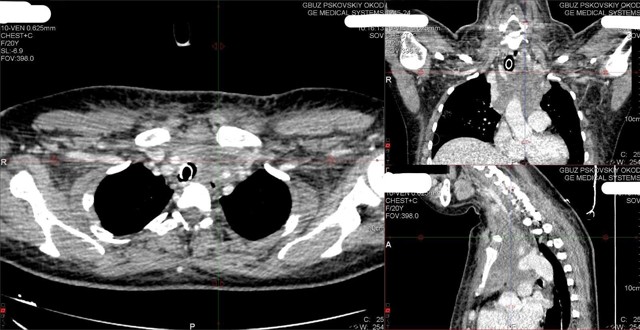

Пациентка обратилась уже в тяжелом состоянии и жаловалась на затрудненное дыхание и одутловатость лица. Причиной стало опухолевое поражение лимфоузлов средостения, которые, превратившись в большой конгломерат с кулак, сдавили трахею пациентки и верхнюю полую вену — очень важный крупный сосуд в грудной клетке.

Псковские онкологи провели исследование опухоли и начали лечение. Сейчас пациентка на пути к выздоровлению, девушка чувствует себя хорошо.